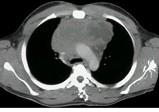

问题 男,17岁,发现颈部肿块1个月,胸片检查、CT检查如图,最可能的诊断为 ( )

选项 A.胸腺瘤 B.畸胎瘤 C.淋巴瘤 D.胸内甲状腺瘤 E.囊状淋巴管瘤

答案 C